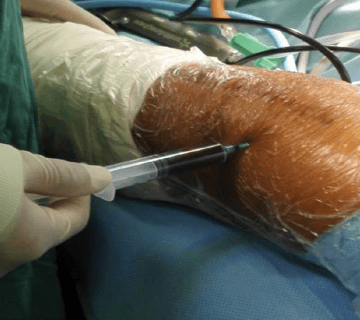

جراحی تعویض مفصل زانو یا (Total Knee Replacement) این جراحی یکی از رایج ترین و موفق ترین روش های درمان آرتروز شدید زانو است. در این روش، بخش های آسیب دیده مفصل زانو (استخوان، غضروف) با قطعات مصنوعی جایگزین می شوند.